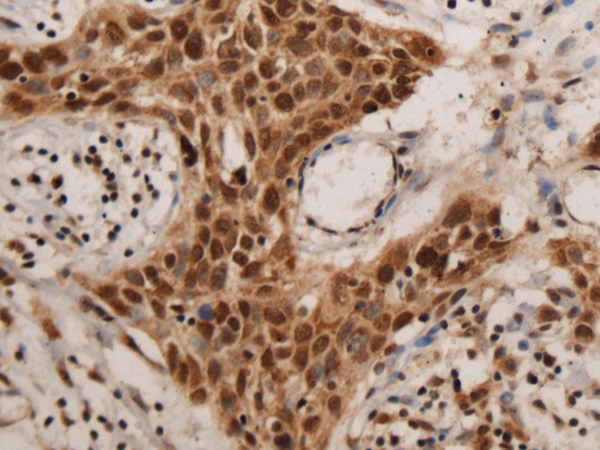

ELISA, IHC

IHC positive control:

Human colorectal cancer and Human esophagus cancer

IHC Recommend dilution:

100-300